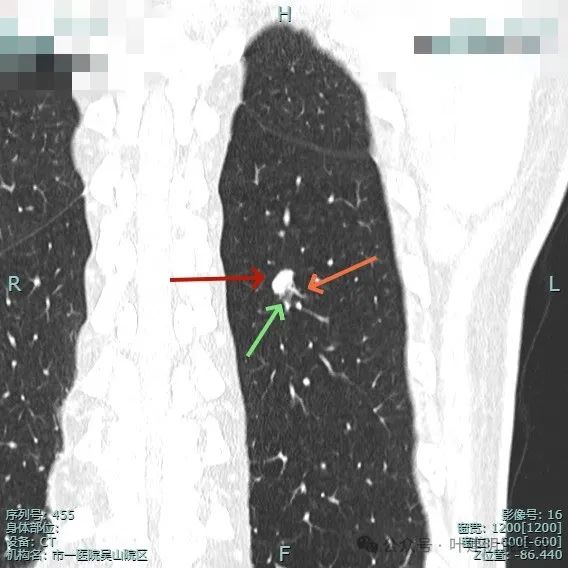

左下背段病灶实性,密度较高,紫色箭头处表面有细锯齿状,桔色箭头示有血管发出分支进入病灶且进入的血管到了结节边上有增粗。

多支血管进入,病灶有膨胀感。